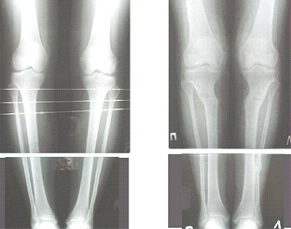

AC> Обратилась дама 25 лет. Вынуждена ходить в брюках из-за genu varum,

AC> что побудило обратиться за коррекцией.

Сейчас это модно (в смысле косметическая коррекция)... Хотя, судя по фото - в данном случае енто вполне оправдано...

Судя по снимку у девушки имеется внутренняя установка надколенников...

Как у нее с торсионным статусом? Бедро? Голень? КТ? Торсиометры? А то, куда будут

смотреть надколенники после вашей коррекции - тоже существенный

косметический момент. Или не так?